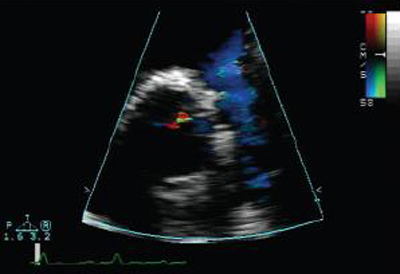

Ecocardiografia com Doppler em um paciente com regurgitação pulmonar após reparo de tetralogia de Fallot, revelando via de saída do ventrículo direito não obstruída. O paciente tem ventrículo direito restritivo

De: Chaturvedi RR, Redington AN. Heart. 2007 Jul;93(7):880-9; usado com permissão